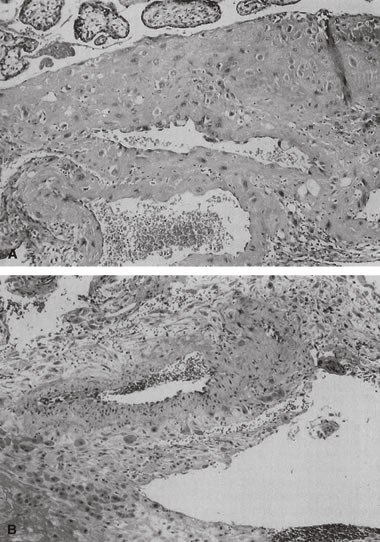

If specimens are cultured for aerobic and anaerobic bacteria in addition to Mycoplasma and Ureaplasma, organisms will be recovered in more than 75% of cases; many are mixed infections. Fusobacterium is an anaerobic filamentous bacterium that results in necrosis of the amnion and is often associated with preterm delivery.15 Group B streptococci may result in “clouds” of bacteria without an appropriate maternal inflammatory response, especially in chronic carrier states (Fig. 5).16,17 Diverse Candida species may also be pathogens (Fig. 6).18 Gram-negative enteric bacteria were recently isolated from between the chorion and amnion in 55% of preterm deliveries, compared with 26% of term births. There was no significant difference in the patterns of isolation of other organisms by gestational age.19 It is likely that different pathogens may be primary in different populations, and an understanding of the local distribution of flora would be important to population-specific applications of microbial surveillance and antibiosis.

Fig. 5. Free membranes with amnion at the top and maternal neutrophils at the bottom, in between which are “clouds” of cocci consistent with broup B streptococci (hematoxylin and eosin, ×40).

Fig. 6. Candida amnionitis. A. Tiny white opaque areas stand out in the translucent cord substance. B. Microscopic section of these areas shows polymorphonuclear leukocytes and inflammatory debris concentrated under the surface. Fungi are difficult to find with hematoxylin and eosin staining. Inset shows numerous yeasts and hyphae revealed by methenamine-silver stain (hematoxylin and eosin, ×75; inset, Gomori's methenamine-silver, ×400). C. Newborn with candidal skin rash.